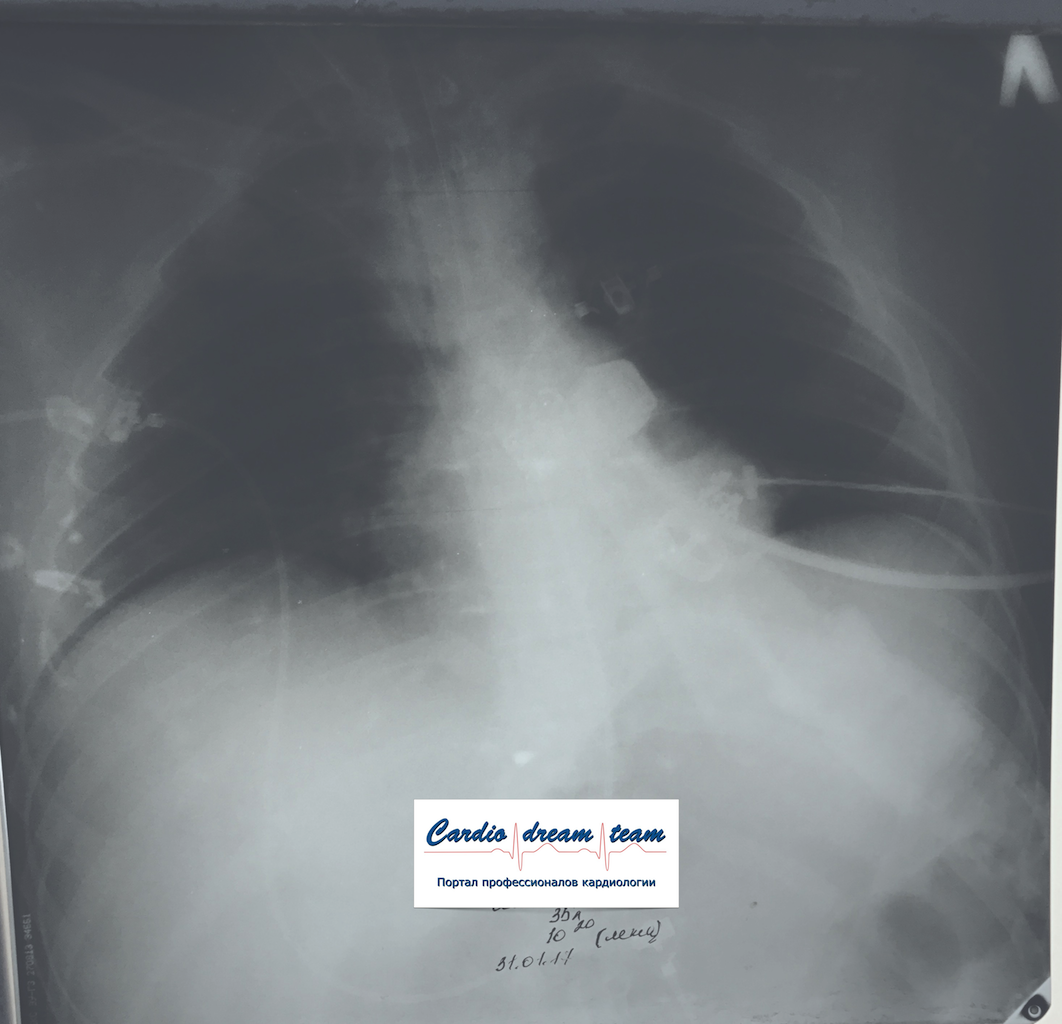

М 35 лет наркоман. Аспирация рвотных масс. До санации и после.

IMG_5519.png

IMG_6456.png